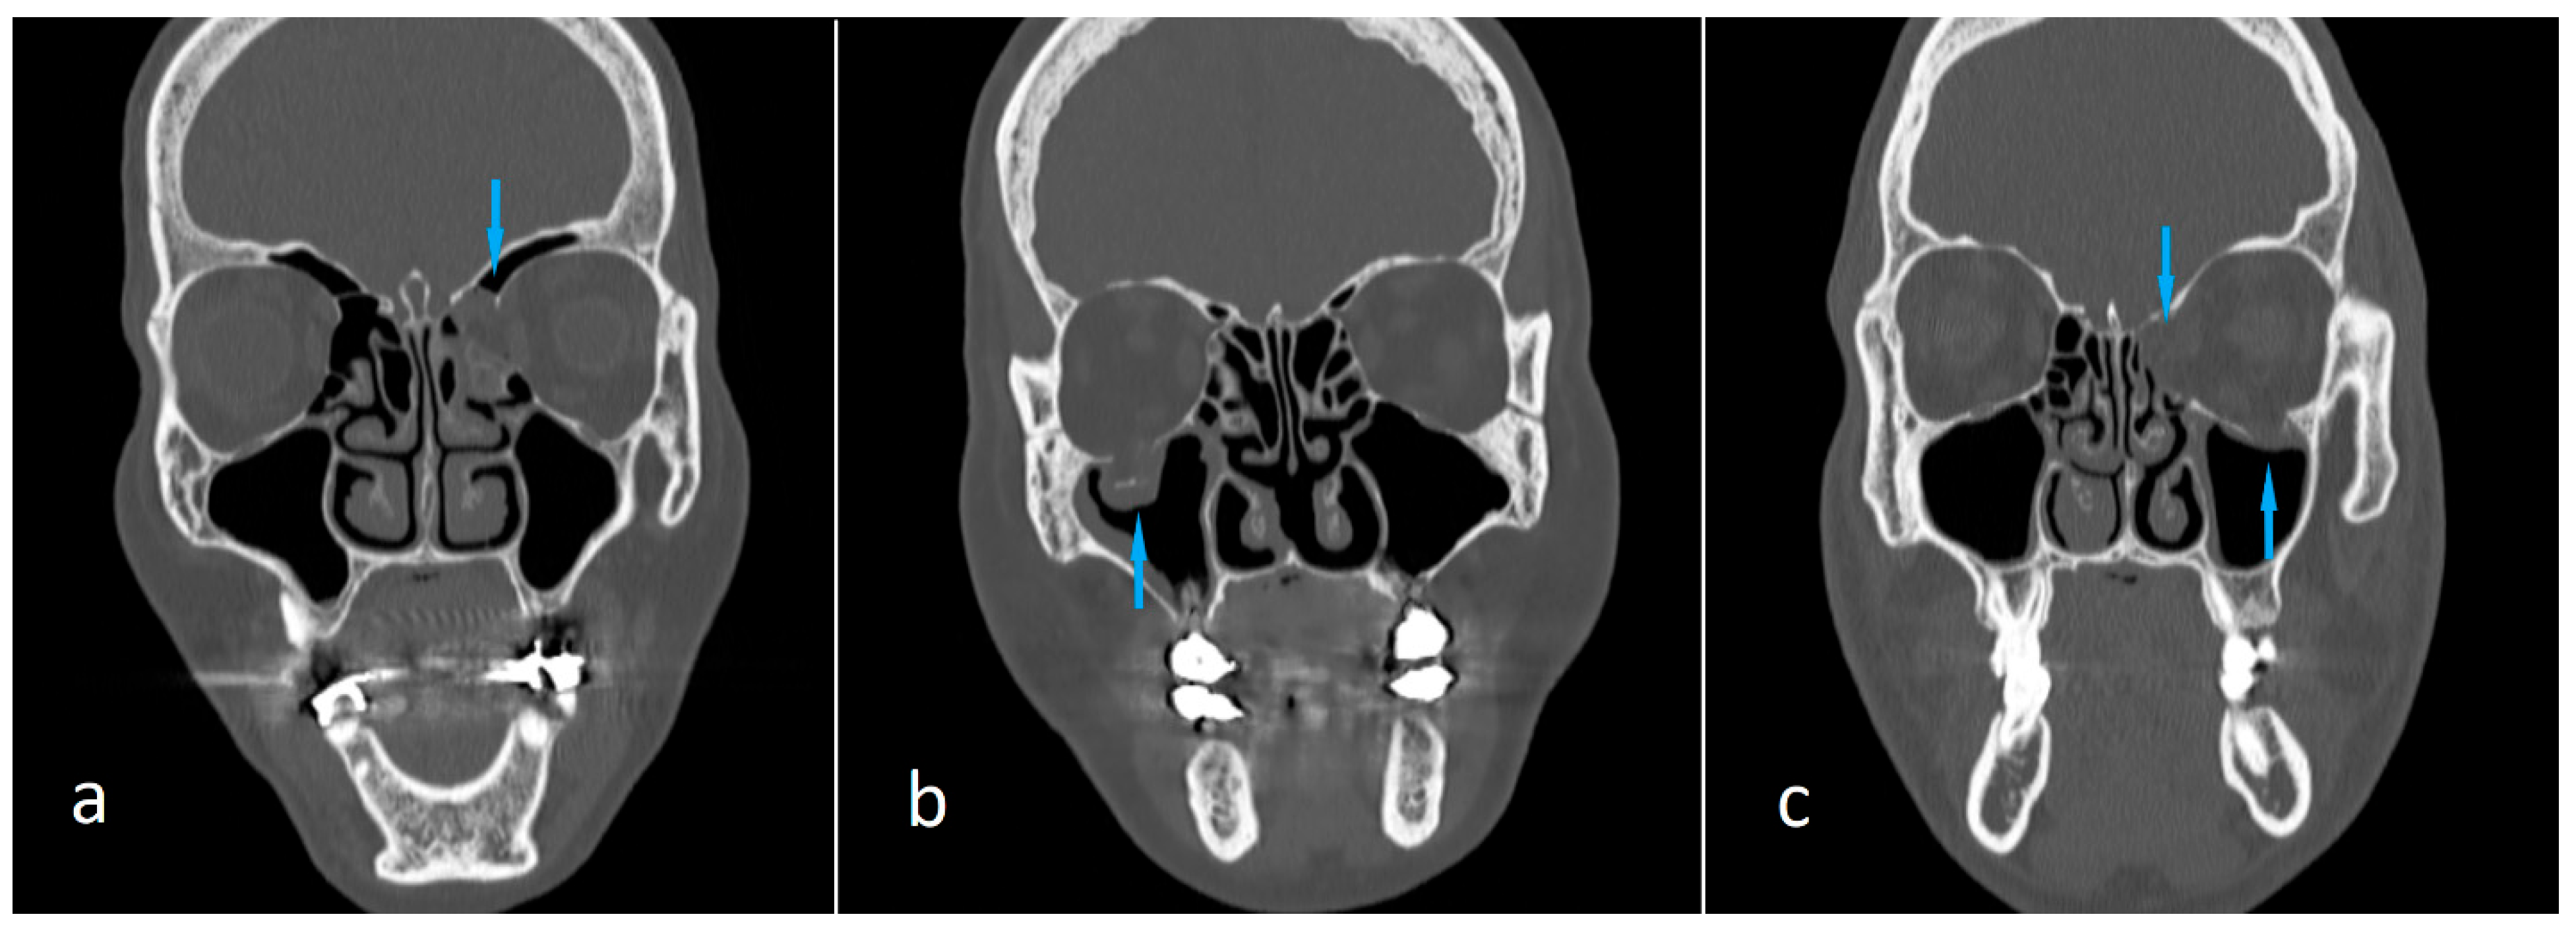

Figure 2. Coronal maxillofacial computed tomography images showing orbital blowout fractures located in the medial wall (a), orbital floor (b), and both the medial wall and orbital floor (c) (arrows).

The predictor variable of the study was ESV, and the main outcome variable was the incidence of OBF. So we compared the case and control groups in terms of mean ESV. Sex was one of the two covariates of the study, and we compared case and control groups in terms of mean ESV separately for both women and men. The other covariate was the fracture location. The case group was divided into subgroups as follows: medial wall fractures, orbital floor fractures, and the fractures in both the medial wall and orbital floor (Figure 2). The mean ESV value of each subgroup was compared with that of the control group.